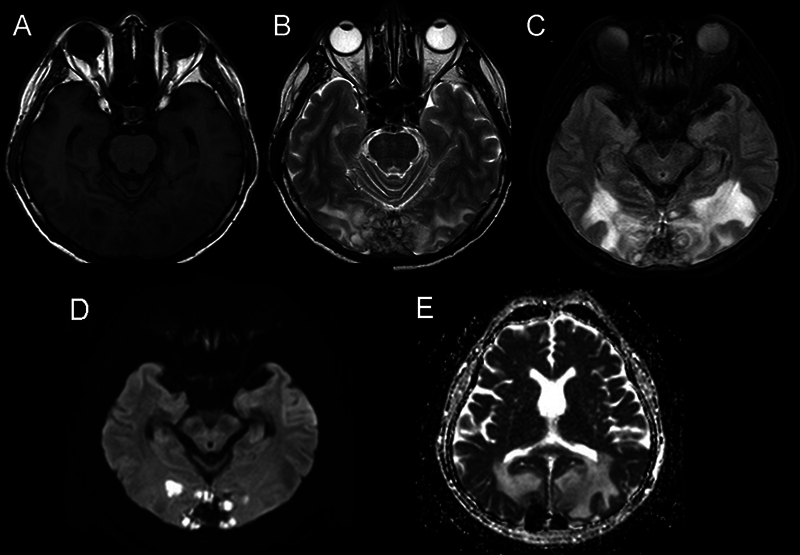

脑曲霉菌病是一种机会性真菌感染,在免疫功能正常的患者中极为罕见。这些感染的主要病因通常涉及鼻腔和血液传播。一名 62 岁的男性患者注重养生,出现间歇性、非进行性枕部头痛、全身阵挛强直发作和意识改变。计算机断层扫描显示,两侧枕叶有多个边缘强化的小病灶,两侧枕叶邻近蝶窦和后上矢状窦汇合处有血管源性水肿。在这个病例中,发现了继发于脑曲霉菌病的上矢状窦血栓形成,这种情况以前从未在这个特定部位确诊过,但可以通过手术干预加以控制。手术切除和抗真菌治疗相结合,取得了良好的疗效。患者的预后很大程度上取决于早期诊断和及时、积极的治疗。

Cerebral aspergillosis is an opportunistic fungal infection that is exceedingly rare in immunocompetent patients. The primary etiological locations for these infections typically involve the nasal cavity and hematological dissemination. A 62-year-old male, focused on wellness, presented with intermittent, nonprogressive headaches in the occipital region, generalized clonic-tonic seizures, and altered consciousness. A computed tomography scan revealed multiple small rim-enhancing lesions in both occipital lobes, with vasogenic edema in both occipital lobes adjacent to the confluence of the sinuses and the posterior superior sagittal sinus. In this case, superior sagittal sinus thrombosis secondary to cerebral aspergillosis was discovered, a condition not previously diagnosed in this specific location but manageable through surgical intervention. A combination of surgical resection and antifungal therapy resulted in favorable outcomes. The prognosis for patients depends significantly on early diagnosis and prompt, aggressive treatment.